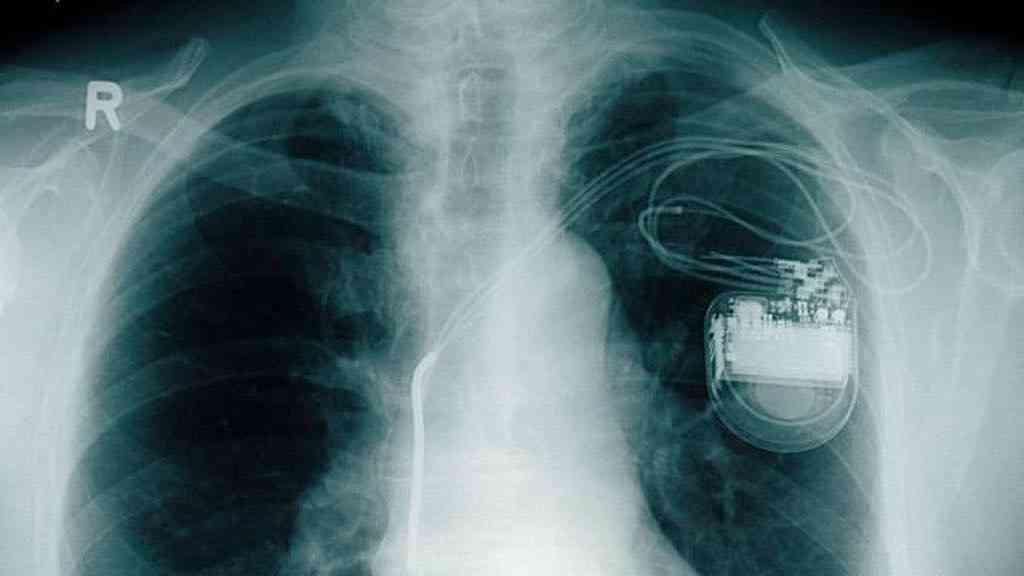

Marca-passo observado em imagem de raio-x: milhões de pessoas no mundo vivem com o implante